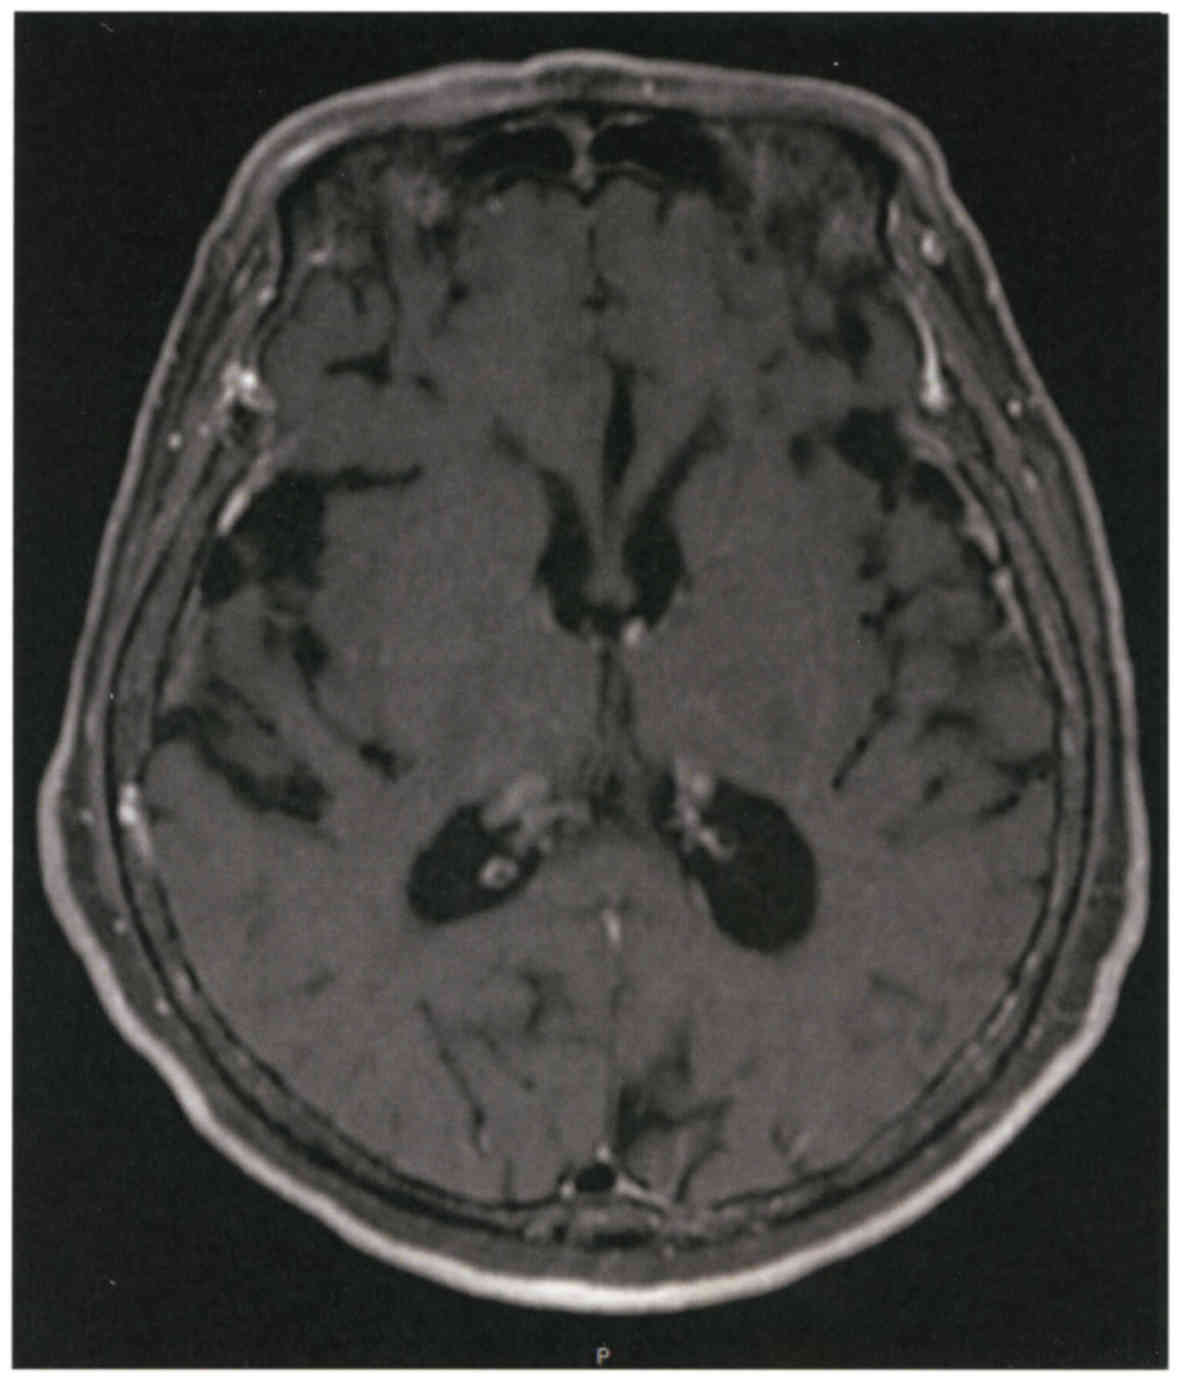

Seven years before admission, a 72-year old non-smoker female, with no relevant family history, received the diagnosis of lung adenocarcinoma, stage pT2N2M0 and underwent partial resection of the upper and middle lobes of the right lung. The post-surgical clinical stage was IIIA and genetic testing disclosed EGFR exon 19 deletion. Thereafter, the patient was treated with standard chemotherapy including cisplatin/carboplatin in combination with gemcitabine but, during the follow-up evaluation 3 years before admission, a metastatic tumor in the right lung was detected by positron emission tomography (PET) study. The patient was then treated with a combination of erlotinib and onartuzumab and then followed up on a maintenance therapy with oral erlotinib (100 mg). Nine months before admission PET examination disclosed the presence of bone metastasis and the patient was then treated with four cycles of chemotherapy including carboplatin and pemetrexed followed by a maintenance therapy with pemetrexed. One month previous to admission, the patient complained of dizziness and a serum test showed increased values of carcinoembryonic antigen (CEA). A magnetic resonance image of the brain revealed multiple brain metastasis with neurological alterations. Combined therapy with docetaxel and ramucirumab was started but a subsequent magnetic resonance imaging showed enlargement of ventricles (Fig. 1). Based on these observations the malignant disease was judged as being in progressive stage, and the performance status of the patient was grade 4 based on the criteria of the Eastern Cooperative Oncology Group (ECOG). At this clinical stage, the patient was referred to our hospital.

Figure 1.

Magnetic resonance imaging of the brain. There was a slight enlargement of the brain ventricles on admission.